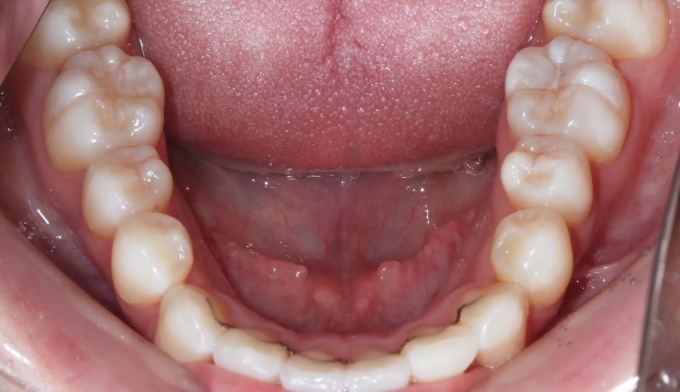

덧니

덧니가 생길정도로 공간이 부족한 경우, 발치교정이 대표적인 방법 중 하나입니다.

하지만 그 필요한 공간의 정도와 안모를 종합적으로 고려하였을때, 비발치로도 충분히 가능한 경우가 많습니다.

이번 케이스도 필요한 공간이 많긴 하지만, 입의 보양이나 각도를 고려하였을 때 비발치로 교정 가능한 경우라 판단되어 발치없이 성공적으로 치아를 배열하였습니다.

총 교정기간은 15개월입니다.